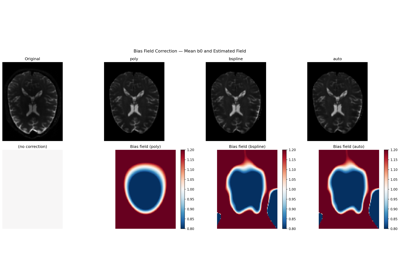

Patch2Self: Self-Supervised Denoising via Statistical Independence

Denoise images using Local PCA via empirical thresholds

Denoise images using Adaptive Soft Coefficient Matching (ASCM)

Denoise images using the Marcenko-Pastur PCA algorithm